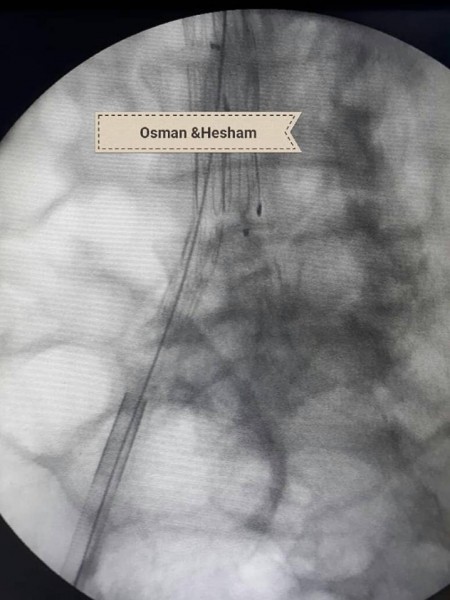

وحول خطوات الجراحة أضاف الدكتور عثمان انه فور إجراء أشعه الدوبلكس للمريض على للشريان الحرقفى الأيسر والشريان الأورطى تبين وجود تمدد ووجود قرحه نشطة بالشريان مع تصلبات شديدة غير مستقرة وانسداد بالدعامة السابقة وكذلك تم إجراء أشعه مقطعية على الشريان الأورطى والطرفين بالصبغة والتي أكدت نفس النتائج ، فكان القرار استخدام دعامات مغطاة للشريان الأورطى والشريان الحرقفى الأيمن وذلك نظراً لأن الوضع الصحي للمريض لا يسمح بإجراء تدخلات جراحية للشريان الأورطى ، ثم تم عمل زرع شريان من الطرف الأيمن للطرف الأيسر لصعوبة شق الدعامة السابقة لاختلاف كبير فى المقاسات التي تم تركيبها للمريض فى وقت سابق .

ومن جانبه أضاف الدكتور هشام أبو العيون مدرس جراحة الأوعية أن تلك الحالة ثالث حاله ايفار EVAR فى صعيد مصر وأول حالة يستخدم بها Aorto-uniiliac system والتي تمت بنجاح منقطع النظير ،وخرج المريض بنبض محسوس بالطرفين وغادر العناية بعد 24 ساعة فى صحة جيدة ودون حدوث اى مضاعفات ، مشيراً أن ذلك تم بفضل جهود الفريق الطبي للعملية والذى تكون من الدكتور محمد جمال مدرس مساعد جراحة الاوعية الدموية إلى جانب فريق التخدير بقياده الدكتور ايمن ممدوح الأستاذ بقسم التخدير والعناية المركزة ، وكذلك أطقم التمريض بالعمليات والعناية المركزة.